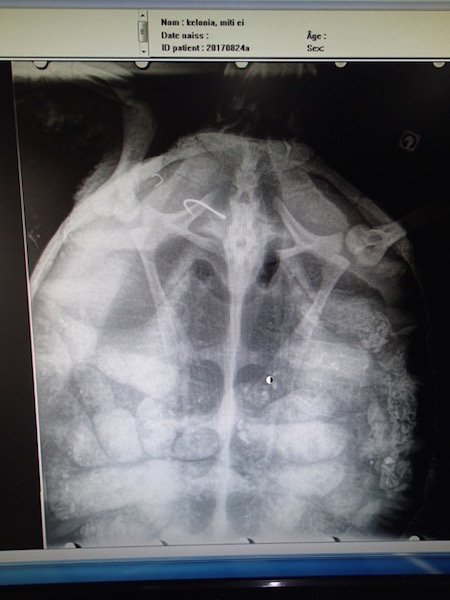

Le centre de soins Kélonia, qui avait gardé Miti de mars à juin 2016, en profite cette fois-ci pour faire des examens complémentaires sur la tortue pour notamment vérifier si elle n'a pas ingéré de plastique. "A, la radio Miti montre un tube digestif bien plein. Si les résultat de sa prise de sang ne signalent rien de nouveau, Miti pourra retourner au Cap pour le plus grand plaisir des apnéistes et des plongeurs, qui ont pris l’habitude de la croiser à La Réunion depuis mai 2008, date où elle a été photographiée pour la première fois par son parrain Hendrik !" écrit Kélonia.